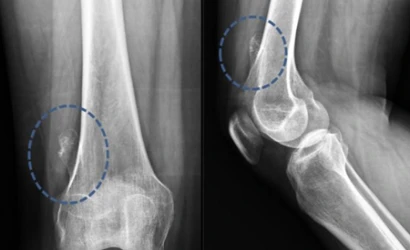

OSTEOKONDROM

Osteokondrom Nedir ?

Osteokondrom, kemik ve kıkırdak dokunun kemik yüzeyinden dışarı doğru büyümesiyle oluşan iyi huylu (be...